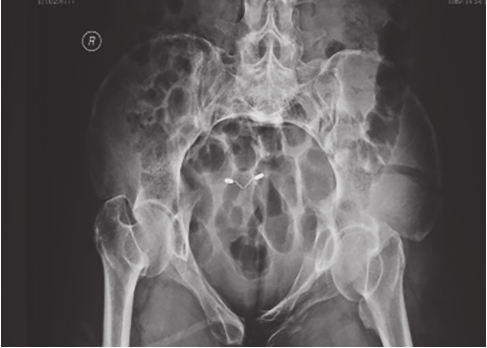

最为常用,患者仰卧,射线呈前后方向垂直投射,骨盆入口边缘与躯干纵轴呈45°~60°夹角。该位像基本能了解骨盆前后环骨折及骶髂关节骨折脱位情况。可用于鉴别骶骨、骨盆髋臼、近端股骨等部位骨折(图2-1)。

图2-1 骨盆前后位X线片

可见左侧骶髂关节骶骨及髂骨面局部骨质断裂,关节间隙增宽,左侧耻上、下支骨折,累及耻骨联合左侧缘。